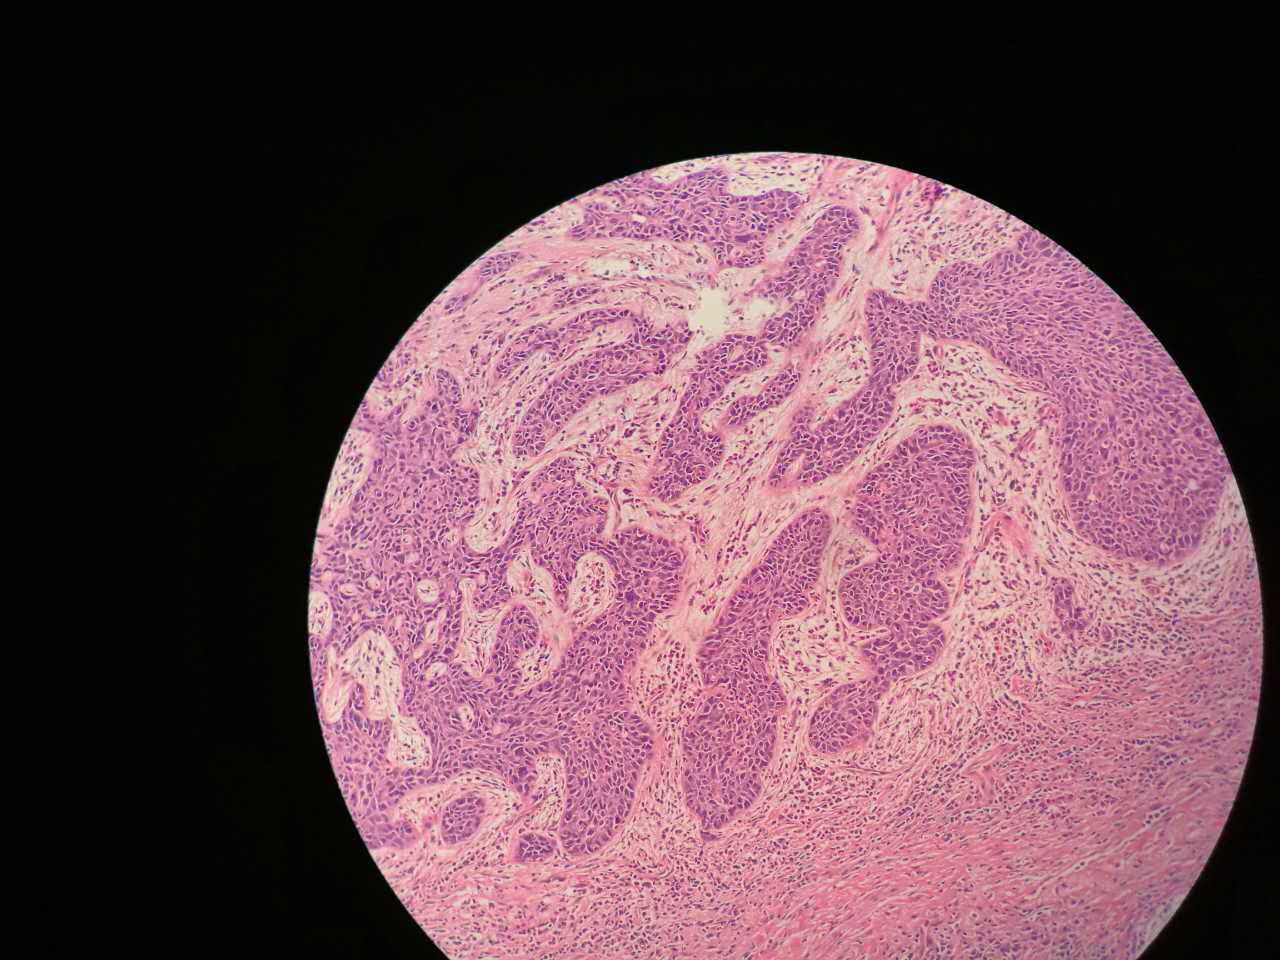

粘液型腺癌

粘液型腺癌是原发肺腺癌中的一种特殊类型

细胞内外含较多粘液

粘液型腺癌,细胞内粘液多,有点儿像支气管的粘液腺

单纯的粘液腺,没有浆液腺

细胞外粘液湖

粘液腺癌起源于细支气管和肺泡

和普通型腺癌位置基本一样

细胞外粘液是白色偏微红

这一幅的上方都是黏液湖

下方是正常肺泡

细胞内白颜色区是粘液,细胞外洋流样的也是粘液(湖)

黏液湖里可以飘着一些细胞,吞噬细胞及肿瘤细胞。

肿瘤细胞飘出去可以种植于肺泡上。

肿瘤细胞堆经常是离开的

中间这一团,整个都是飘过来种植长成这样

这在进展后期特别多见

早期飘散常很近

这个是早期结节状的粘液型腺癌

随着粘液近距离播散

早期粘液漂散也是近距离的,右侧肺泡里干净,没粘液,粘液产量有限,并且互相有黏连牵制。

所以结节性粘液腺癌边界一般较清楚